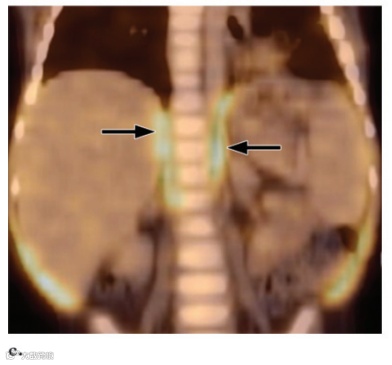

图16. 粒细胞集落刺激因子 (G-CSF) 对一名15岁霍奇金病女孩的效果。两轮化疗后进行FDG PET/CT 检查。

MIP FDG PET 图像显示弥漫性骨骼和脾脏摄取,这一发现反映了粒细胞集落刺激因子 (G-CSF) 诱导的造血作用。

脾脏是免疫系统的重要组成部分,并且具有多种功能,包括清除荚膜细菌、吞噬作用以及产生炎症物质和免疫球蛋白抗体。据推测,脾脏活动的广泛增强反映了脾外感染时该器官的葡萄糖消耗增加。外部放射治疗几个月后,可以观察到骨髓FDG摄取减少。这种现象归因于脂肪组织取代骨髓。通常,正常骨骼中不会发现FDG摄取。然而,骨骼未成熟的儿科患者可能在骨骺和骨突中出现生理线性摄取(图17)。